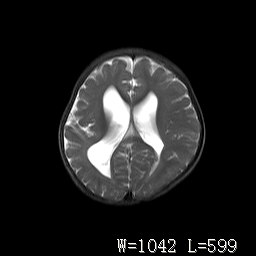

标题: PED3252:脑室增大。

女,3岁,3岁不会说话,阵发性抽搐、自伤。

倒数第3附图不是这个病人的吧!考虑脑白质发育不良可能。

右侧额叶发育不良!

右侧额叶发育不良。

右侧额叶发育不良